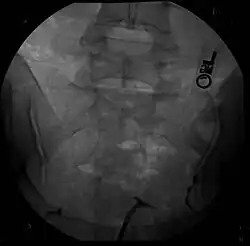

Besides a physical examination, the physician will need imaging techniques to determine the character of the malformation: gynecologic ultrasonography, pelvic MRI, or hysterosalpingography. A hysterosalpingogram is not considered as useful due to the inability of the technique to evaluate the exterior contour of the uterus and distinguish between a bicornuate and septate uterus. In addition, laparoscopy and/or hysteroscopy may be indicated. In some patients the vaginal development may be affected.